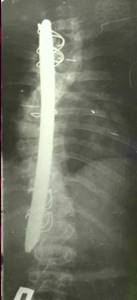

| Различные варианты однопластинчатого эндокорректора |

| Двухпластинчатый эндокорректор с многоуровневой фиксацией |

| Больной З-ч. 13 лет Сколиотическая деформация II степени грудного отдела позвоночника. Рентгенограмма позвоночника до операции |

Результат оперативного лечения. Коррекция 100% |